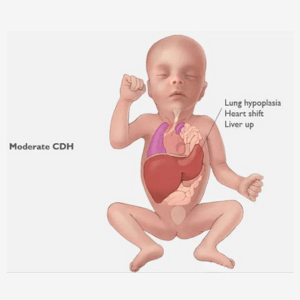

Congenital diaphragmatic hernia (CDH)

Diaphragmatic hernia